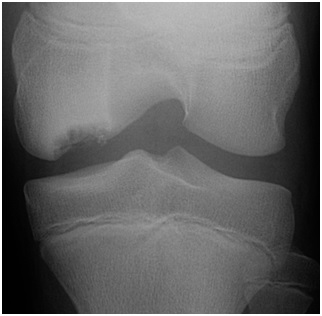

Tunnel view of osteochondritis dissecans

From the collection of H. Chambers, MD